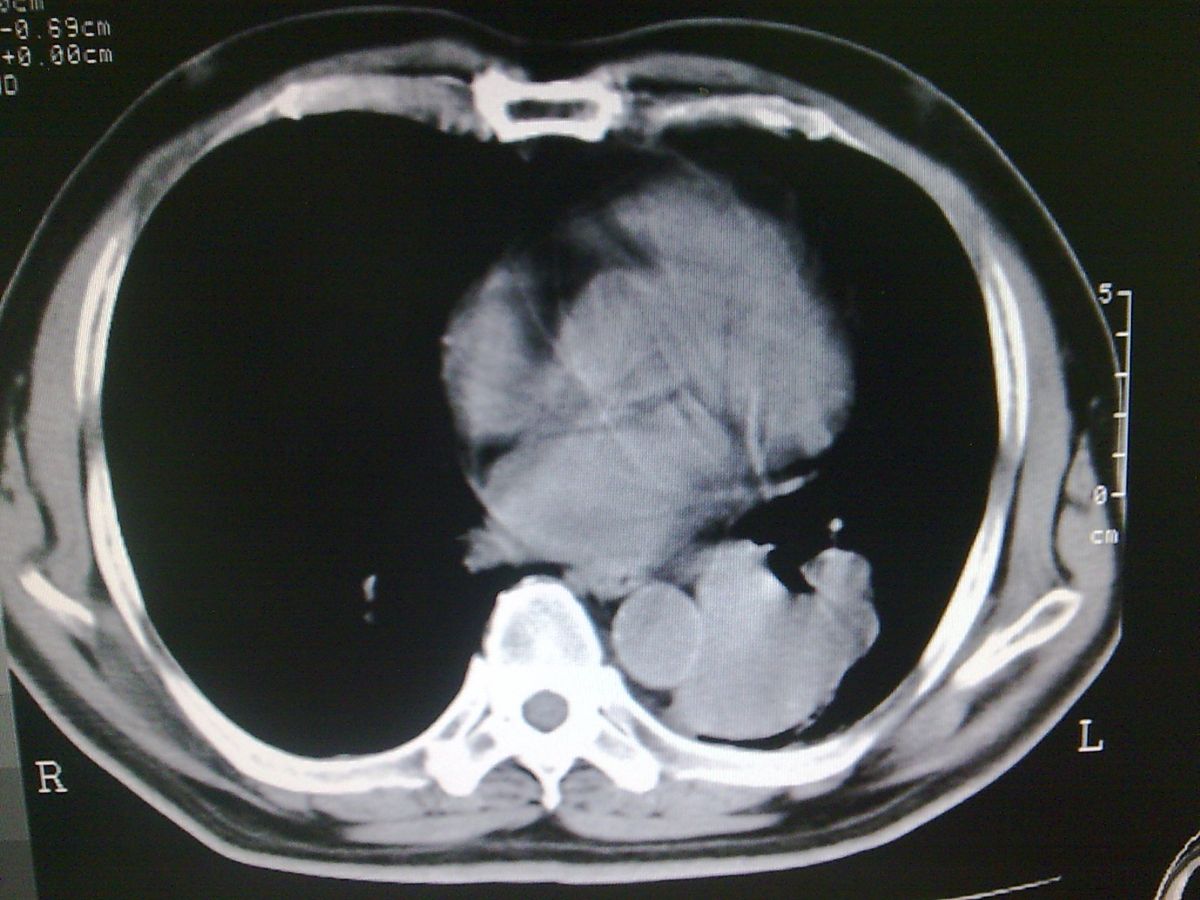

标题: CT19282:男性,70岁,咳血, [打印本页]

标题: CT19282:男性,70岁,咳血,

图片少了些,考虑周围性肺癌

考虑周围性肺癌

周围型肺癌。

考虑左下肺周围性肺癌。

考虑左下周围型肺癌可能性大。

考虑左肺下叶周围型肺癌可能。